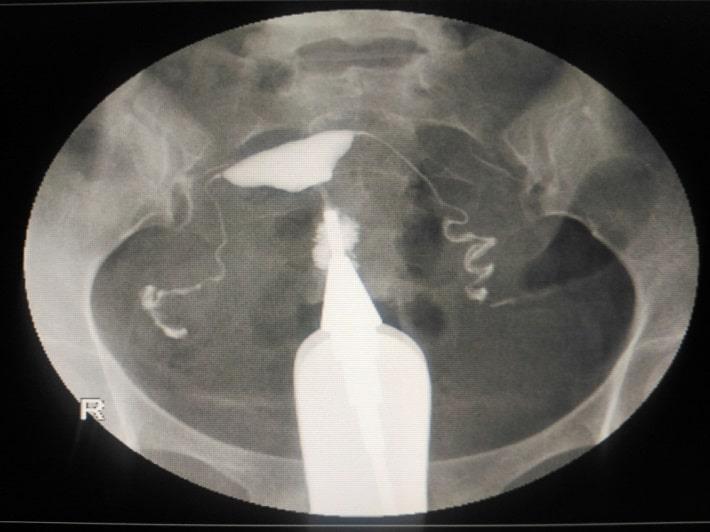

צילום רחם הוא בדיקת רנטגן שנעשית לרוב במסגרת בירור של בעיה גניקולוגית. בבדיקה מתקבלת פלואורוסקופיה – שיקוף, סדרה של צילומי רנטגן רציפים, המשרטטים את הצורה הפנימית של הרחם ושל החצוצרות. בבדיקת צילום רחם מוחדר צינור דק דרך הנרתיק וצוואר הרחם, ולאחר מכן מוזרק חומר ניגוד לרחם, שבאמצעותו ניתן לקבל תמונה של צבע לבן בצילום הרנטגן. הנוזל, הצבע, עובר לתוך הרחם ולאחר מכן לתוך החצוצרות. אם ישנה חריגה בצורת הרחם - היא תסומן בעזרת הצבע; אם החצוצרה פתוחה, הצבע ימלא אותה בהדרגה. לבסוף הצבע נשפך לחלל האגן, שם הגוף סופג אותו[1].

מהלך הבדיקה המטופלת ממוקמת מתחת למכשיר פלואורוסקופיה (מצלמת רנטגן). ספקולום מונח בתוך תעלת הנרתיק של המטופלת ולאחר מכן מנקים את צוואר הרחם. בשלב הבא מוחדרת צינורית (קנולה) לתוך פתח צוואר הרחם. הגניקולוגית תמלא בעדינות את הרחם בנוזל המכיל יוד (חומר ניגוד שניתן לראות בצילום הרנטגן) דרך הצינורית. הניגודיות תוצג בצבע לבן בתמונה והיא תראה את הצורה של הרחם כשהנוזל עובר מהצינורית לתוך הרחם ודרך החצוצרות. כאשר חומר הניגוד נכנס לצינורות החצוצרות, הוא צובע אותן ונשפך החוצה בקצוות, אם החצוצרות פתוחות. במקרה שבהן החצוצרות חסומות, הן לא יצבעו בצבע הניגוד. חריגות בתוך חלל הרחם יכולות גם הן להתגלות בצילום רחם, כאשר תנועת הנוזל מופרעת על ידי החריגות. הליך זה אינו נועד להעריך את מצב השחלות או לאבחן אנדומטריוזיס, ואינו יכול לזהות שרירנים הנמצאים מחוץ לחלל רירית הרחם, בחלק השרירי של הרחם, או בחלק החיצוני של הרחם. לעתים קרובות, יהיה צורך שמטופלת תשנה את מיקומה על השולחן במהלך הבדיקה[5].